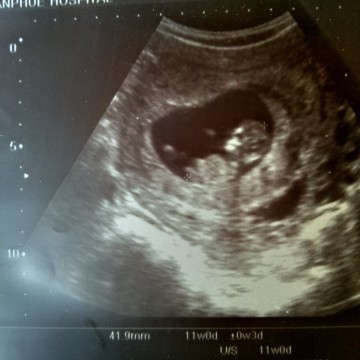

u/s ครั้งแรกตอน 6 weeks เจอแค่ถุงตั้งครรภ์ค่ะ คุณแม่ตั้งตารอวันนี้มาเป็นเดือนเพราะอยากเห็นลูกจะแย่ ตอนนี้ 10 weeks คุณแม่เห็นหนูแล้ว ดิ้นเก่งมากคงแสบน่าดู คุณหมอแอบแซวให้หนูอยู่นิ่งๆด้วย เพราะคุณหมอจะวัดขนาด 😂

3สิงหาภาพตอน11วีค ตอนนี้จะเข้า15วีคแล้วค่ะ

กำหนดคลอด 16 สิงหา ตอนซาวด์ ได้11 w ค่ะ

ของเรากำหนดคลอด 25 สิงหาคม ค่ะ ตอนนี้ 11Week

29 ส.ค.ค่ะคุณหมอให้ภาพนี้มาค่ะ

ภาพตอน 10w3dค่ะ กำหนดคลอด 17สิงหา 🥰🥰🥰